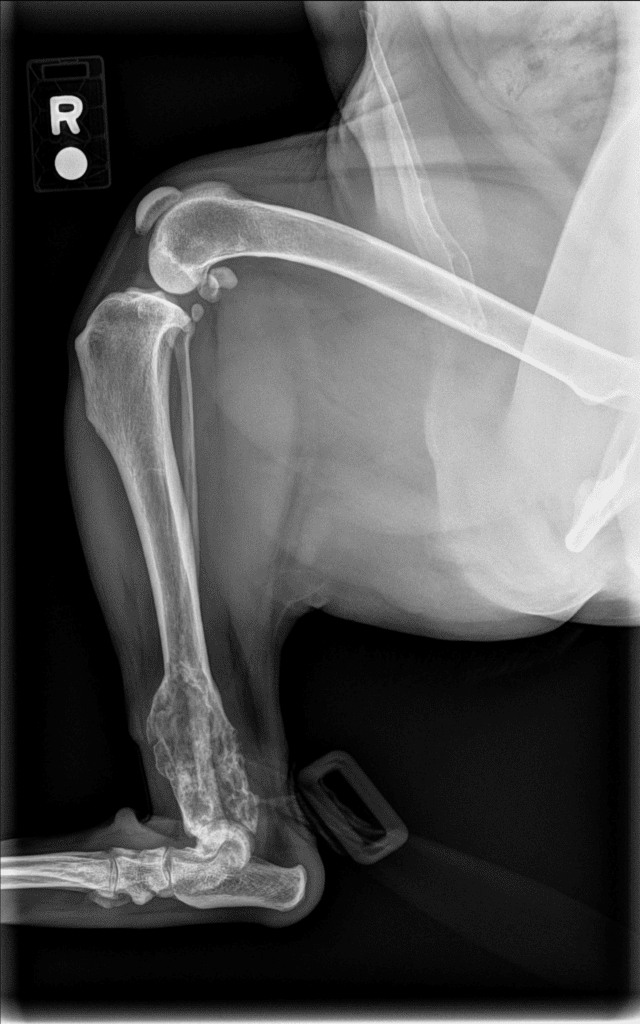

Kodak was seen by Dr. Cross on December 4th for a right hindlimb lameness, and he was diagnosed with a right distal tibial bone tumor. His chest radiographs were normal. Dr. MacDougall did a hind limb amputation on December 8th, and he recovered beautifully. He started chemotherapy with Dr. Cletzer in early January, and has now graduated from treatment! He will be rechecked every 3 months for a physical exam and chest radiographs, but has done so well for all his treatment! He is the sweetest Pittie boy!